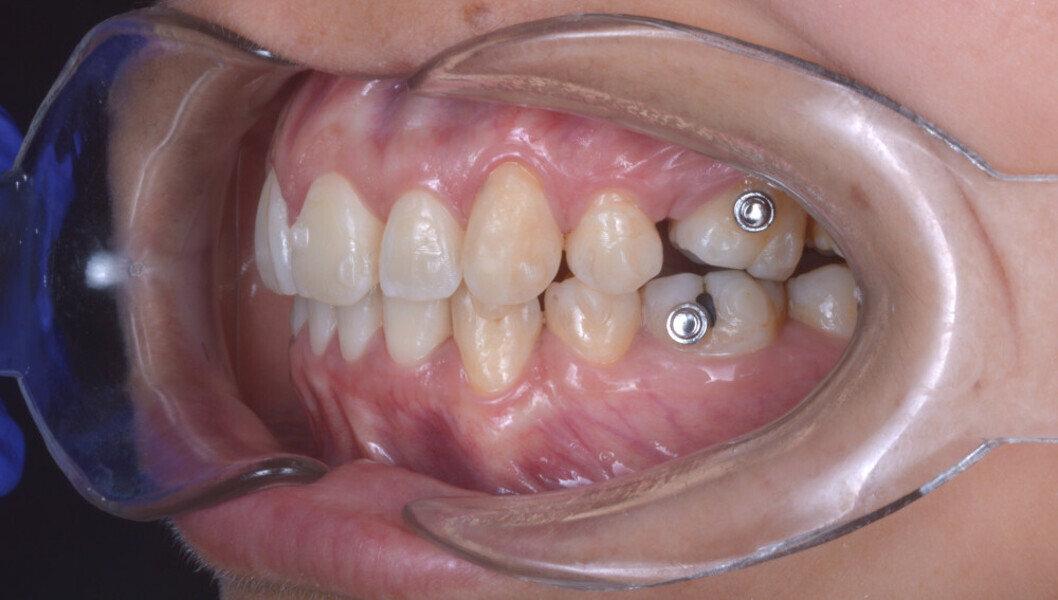

Before the aligner treatment began, the maxillary and mandibular second premolars were extracted to create space. With orthodontic treatment, distalisation of the anterior teeth was achieved by employing maximum mandibular anchorage and moderate maxillary anchorage (Figs. 5–7). At the end of the treatment, a stable bilateral Class I occlusion had been achieved, as well as normal inclination and retrusion of the anterior teeth, consequently improving the profile (Figs. 8–10).

Once the orthodontic treatment had been completed, botulinum toxin was injected bilaterally into the masseter muscle and an anterior portion of the temporalis muscle. In the first session, three injections were performed in the masseter muscle, administering 2.5 U in the most superior point and 5.0 U in each of the two lower points, a total of 12.5 U per masseter. Then, 10 U of botulinum toxin was injected into the anterior portion of the temporalis muscle in this same session. After 14 days, a second session was performed. Because the patient presented with slightly greater hypertrophy on the right side compared with the left side, 5.0 U of botulinum toxin was injected into the right masseter and 2.5 U into the left masseter.